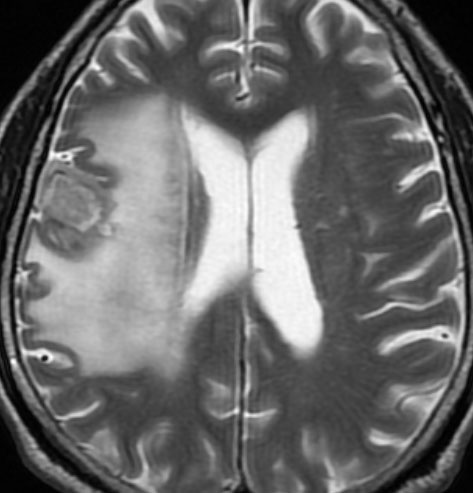

60代後半の患者さんで右前頭葉転移性脳腫瘍です。けいれん発作で発症しました。

定位放射線治療前

典型的な脳転移のMRIです。腫瘍は,リング状にガドリニウム増強され,内部が腫瘍壊死になっています。腫瘍周囲の脳浮腫がとても強いのが転移の特徴的画像所見(右側のT2強調画像)です。この転移巣に対して,35グレイ・5分割の定位放射線治療が加えられました。